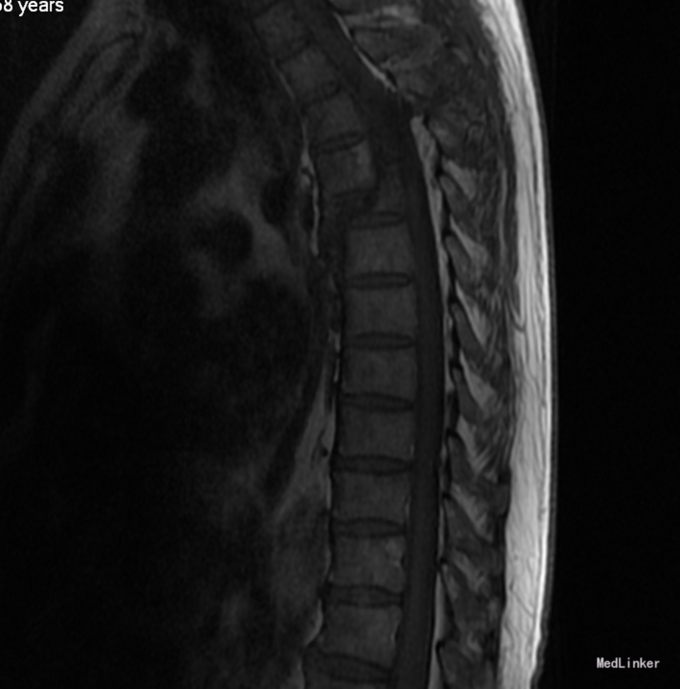

患者于2014-08-13日11:30左右骑摩托车摔倒,伤后一过性意识不清,清醒后感觉胸部疼痛,双下肢活动受限,急诊送至盘锦市宽甸县中心医院,行胸CT、头CT、胸椎三维CT,提示为胸椎骨折,急诊行面部伤口清创缝合,具体治疗不详。患者及家属为求系统治疗,急来我院,急诊予以行辅助检查,提示:胸椎骨折;急诊以“多发外伤”为主诊断收入我科.

平乳头以下感觉减退,平耻骨联合以下感觉运动消失。上臂肌力(R5,L5),前臂肌力(R5,L5),手掌掌屈肌力(R5,L5),手掌背伸肌力(R5,L5)。双手握力(R5,L5)。髂腰肌肌力(L0级,R0级),伸膝力(L0级,R0级),足背伸力(L0级,R0级),足跖屈肌力(L0级,R0级),

诊断:胸3-6椎体骨折,胸髓损伤,双下肢全瘫。 入院后完善检查,查无手术禁忌症后行胸椎骨折后路切开复位椎板减压椎弓根钉内固定术